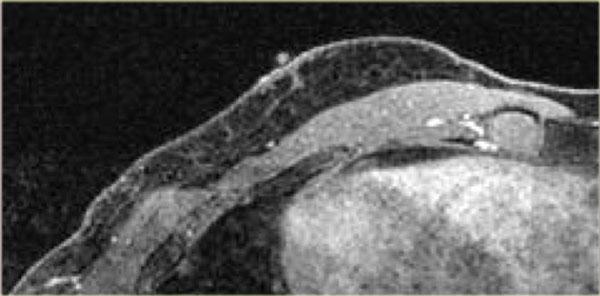

Bên trái là hình ảnh chuỗi xung T2W có xóa mỡ và chuỗi xung T1W sau tiêm thuốc tương phản từ Gadolinium có xóa mỡ.

Một bác sĩ chẩn đoán hình ảnh không quen đọc nhũ ảnh nam giới đã chỉ định MRI để giải quyết vấn đề.

Rõ ràng MRI này được thực hiện vì lý do không phù hợp.

MRI không nên được sử dụng để giải quyết một vấn đề có thể được giải quyết bằng nhũ ảnh.

Dù sao, MRI cũng cho thấy hình ảnh gynecomastia thể nốt.